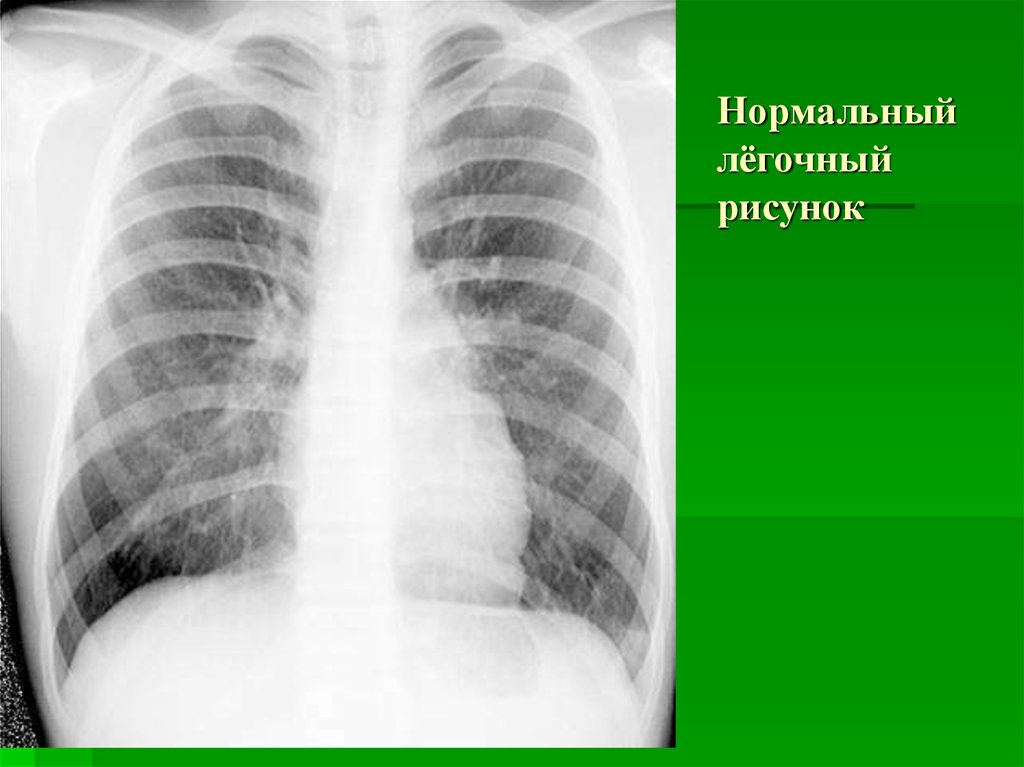

Фотографии, демонстрирующие обнаруженное усиление легочного рисунка

Раздел: Фотодневник открытий